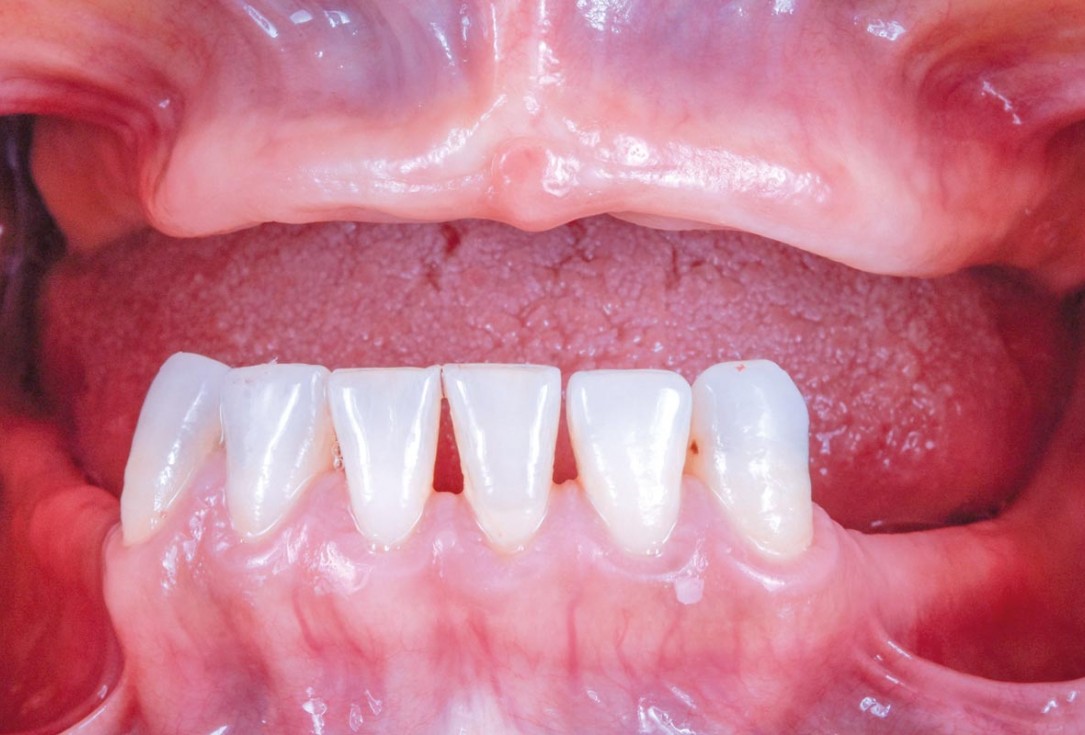

Initial view of the case. Discoloration of 1.1 and mild class I gingival recession